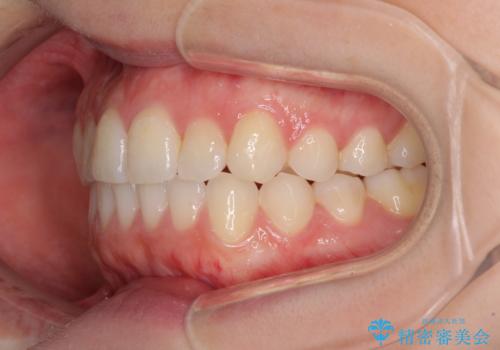

前歯のクロスバイトをインビザライン矯正で改善

- 前歯のデコボコと上下のクロスバイトを気にして来院された患者様です。

インビザラインを用い、IPR(歯と歯の間を削る)と歯列全体を拡大させることで、歯並びを整えていくこととしました。

上の前歯が下の前歯を乗り越える際、奥歯がほとんど咬めない時期があり、乗り越えた後も、インビザライン特有の奥歯の咬みにくさが続きました。

咬み合わせ改善のために治療期間を要しましたが、最終的に奥歯はしっかりと咬めるようになりました。